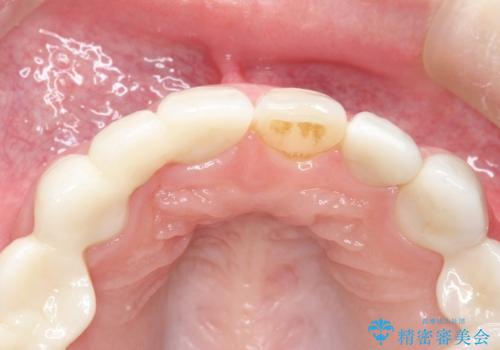

- 昔装着したかぶせ物が、不自然なのでやりかえたいとのことで来院されました。

前歯にレジン前装冠(保険内)が装着されており、自然な透明感がありません。

オールセラミックによるやりかえを行いました。

色調もまわりの歯に合わせて、形態も患者様のご希望に沿うように製作させていただきました。